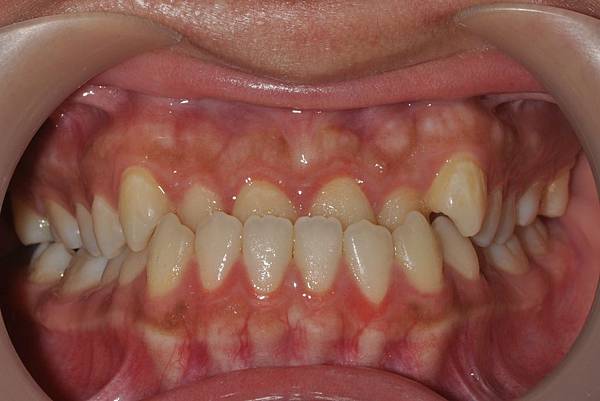

戽斗下唇突出改善案例

本案例因為考量到患者下唇突出

便建議拔除上下四顆小臼齒將

下唇內收

也改善了

前牙錯咬

的問題~

治療前/治療後

-以上案例由林昇進醫師提供